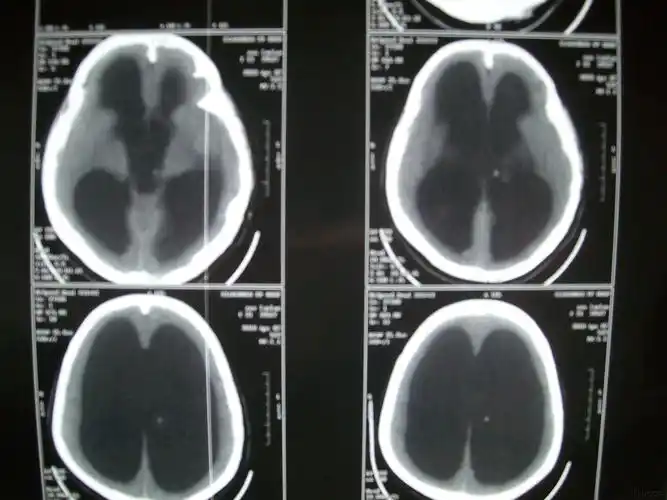

【读片】脑积水 [病例帖]

脑积水一例

李春志 男 64 脑积水 3-2脑室腹腔分流

2017年10月19日,在山西省某三甲医院复查头颅ct提示:"脑积水较前增加"

罕见脑积水病例